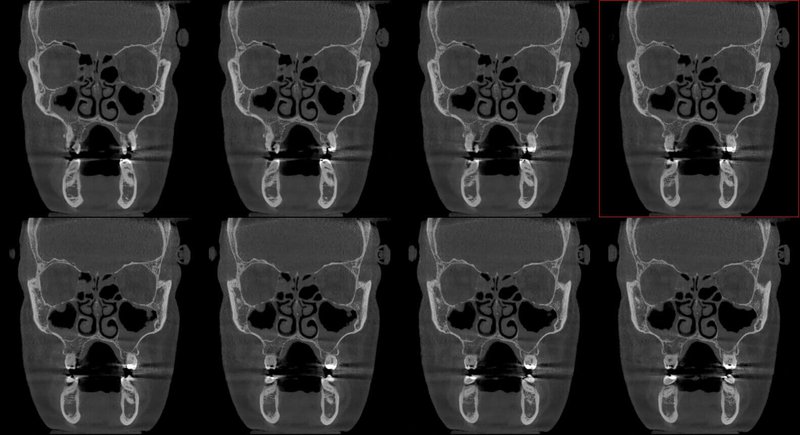

GIANO HR – универсальное обновляемое устройство от NewTom для всех задач, связанных с радиографией. Благодаря полному диапазону опций 2D и 3D исследования для стоматологии оно предлагает множество особых трехмерных обследований для челюстно-лицевой хирургии, оториноларингологии и осмотра шейного отдела позвоночника. Визуализация только наивысшего качества с технологиями и опытом NewTom

NNT – программное обеспечение NewTom, предоставляющее несколько специальных режимов применения для имплантологии, эндодонтии, пародонтологии, челюстно-лицевой хирургии и радиографии. Это мощное технологически новейшее устройство, разработанное, чтобы снимать и обрабатывать изображения в несколько простых шагов для получения информации, необходимой для конкретного подробного диагноза пациенту. Продвинутое устройство, дающее врачу специальные инструменты для измерения анатомической области (расстояния и углы), нахождения нижнего альвеолярного нерва и замера объема верхних дыхательных путей.

NewTom GiANO HR новейшая модель была официально представлена на международном конгрессе радиологов ECR 2018 в марте в Вене. Благодаря обновленным системам механики и запатентованным механизмам работы аппарат отличается от своих сверстников Высочайшим качеством получаемых изображений, как 2D, так и 3D. Лучшее качество снимков и мы отвечаем за это! Этот аппарат заменит три аппарата! Панорамный аппарат, цефалометрическая приставка и конусно-лучевая компьютерная томография интегрированы в единую платформу. В комплекте детектор для выполнения 3D исследований с захватом области 13х16 см, Сьемный 2D CMOS детектор для выполнения панорамных исследований, и ТРГ.